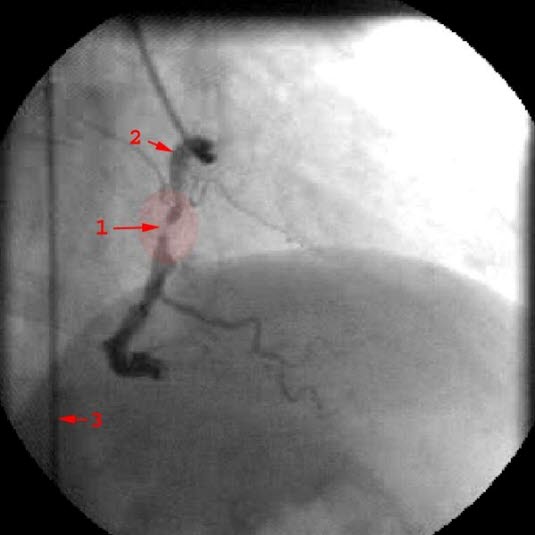

Stenose i høyre koronararterieTrombolyse betyr å løse opp en trombe, det vil i denne sammenhengen si løse opp den pluggen som tetter til koronararterien og fører til hjerteinfarkt. Ved trombolyse benyttes medikamenter som sprøytes inn i blodet før fortetningen i blodåren har rukket å bli fast og organisert. I beste fall kan man med denne metoden klare å åpne blodåren før det har skjedd varig skade. Dersom det likevel oppstår skade, er det vist at behandlingen fører til at skaden reduseres og begrenses i omfang, med andre ord at hjerteinfarktet og derved skaden på hjertet blir mindre.